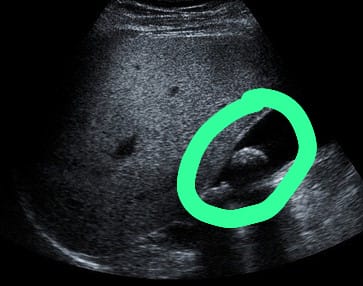

膽結(jié)石的形成與脂肪攝取有關(guān),肥胖人士是高風(fēng)險(xiǎn)群組,蕭醫(yī)生解釋:「肥胖人士膽汁中有較高膽固醇濃度及分泌,且膽固醇合成機(jī)率也較高,故容易形成結(jié)石。除此之外,懷孕婦女由於膽汁飽和度增加,加上女性荷爾蒙的生理作用及膽囊弛張性(atonic)收縮不良,易使結(jié)石情況發(fā)生。在藥物方面,長(zhǎng)期服用避孕丸,及停經(jīng)後使用激素,臨床上發(fā)現(xiàn)有明顯較高的結(jié)石發(fā)生率。糖尿病人也易產(chǎn)生結(jié)石,一般歸因於膽汁中膽固醇分泌過(guò)多,及膽囊運(yùn)動(dòng)性不全(dyskinesia)?!鼓懡Y(jié)石沒(méi)有明顯癥狀,必須透過(guò)醫(yī)學(xué)檢查判斷是否患有膽結(jié)石,蕭醫(yī)生表示:「腹部X光檢查簡(jiǎn)單快捷,但若膽石過(guò)於細(xì)小往往不能察覺(jué)。腹部超聲波是最常用來(lái)查看膽石的檢查,可以查看其存在、位置、膽囊有否發(fā)炎,然而若病人腹部脂肪較厚會(huì)減低檢查的準(zhǔn)確性。腹部電腦掃描或磁力共振檢查除了膽囊狀態(tài),也可檢查腹部?jī)?nèi)各個(gè)器官,準(zhǔn)確性不受病人體形影響。內(nèi)視鏡超聲波可以確認(rèn)膽石位置以及膽囊膽管狀態(tài),不過(guò)具有入侵性風(fēng)險(xiǎn),必須經(jīng)過(guò)??漆t(yī)生評(píng)估,有需要才安排進(jìn)行。」